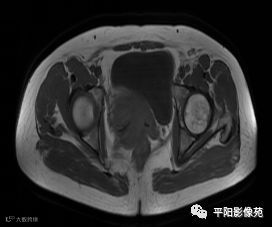

MRI表现

T1轴位

T2轴位

(宫腔内见金属节育环伪影)宫颈区见不规则形等T1稍长T2信号软组织肿块,DWI序列呈明显高信号,大小约为3.87cmX2.64cm,双侧宫颈基质低信号环连续性中断,病灶向子宫右后上方生长,周围脂肪间隙模糊,增强扫描明显强化,强化程度低于子宫及宫颈实质;子宫后方、子宫直肠间隙见不规则形长T1长T2信号软组织肿块,DWI序列呈高信号,大小约10.12cmX4.82cmX10.29cm,病灶呈分叶状,向下方生长与宫颈分界不清,与直肠分界尚清,增强扫描明显不均匀强化。